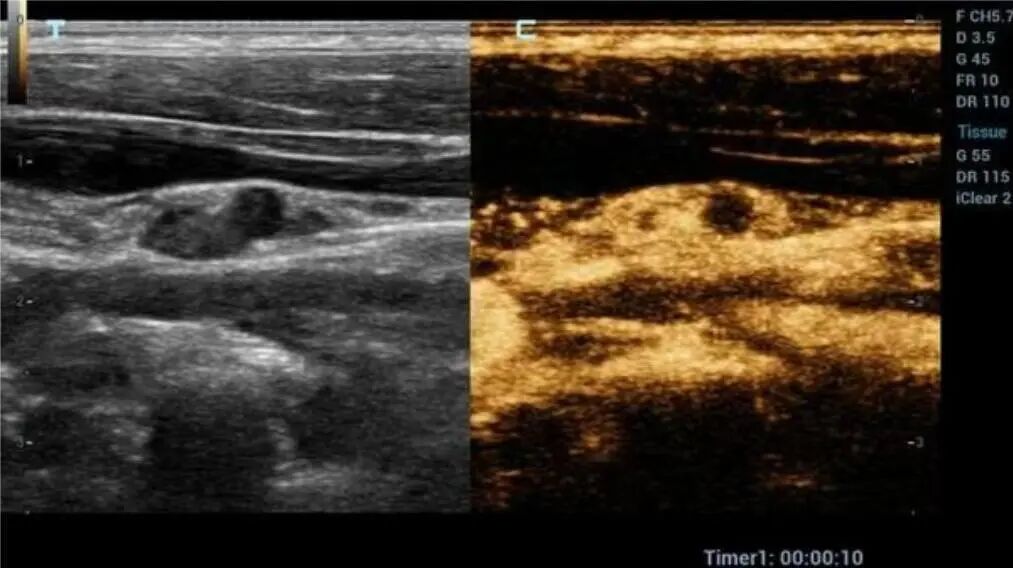

多年来,贵州航天医院各科室紧跟医学前沿,不断强技术、补短板,大力开展新技术、新项目,完成了许多高精尖、高难度、本地区“首例”的技术,填补了医院医疗技术空白,满足了群众日益增长的医疗需求。 复杂性双胎超声监护耗时耗力,技术难度大,风险高,为填补本地区复杂性双胎的超声监护技术空白,我院超声科在遵义市率先开展了此项技术,有效满足了双胎孕妇产检需求,保障了双胎新生儿的平安健康。 本期,我们将为大家带来超声科特色技术——复杂性双胎的超声监护。 案例分享 案例一 28岁的孕妇,自然受孕,怀有单绒毛膜双羊膜囊双胎(MCDA),在我院定期产检的过程中,孕32周超声检查发现两个胎儿的大脑中动脉血流流速(MCA-PSV)相差>0.7倍数的正常值(MoM),高度怀疑发生了双胎贫血红细胞增多序列征(TAPS)。为进一步明确诊断,产科立即组织超声科、手术室、新生儿科等科室进行多学科会诊(MDT),诊断为:双胎贫血红细胞增多序列征(TAPS),在征得孕妇及其家属的同意后,决定提前分娩,及时保障了两名胎儿的生命和健康。 双胎大脑中动脉血流 双胎贫血红细胞增多序列征(TAPS) 案例二 一名26岁的孕妇,是完全双角子宫,且为左侧子宫妊娠,怀有单绒毛膜双羊膜囊双胎(MCDA),一直在我院规律产检,孕16周时,超声检查发现双胎生长不一致,体重相差超过25%,考虑子宫畸形合并早发选择性胎儿宫内生长受限。孕妇在咨询相关上级医院专家后,得到减胎的建议,又前来我院咨询,在我院超声科和产科的合作下,查阅了大量文献、认真评估检查报告后,建议孕妇继续双胎妊娠。在规律、严密的超声监护下,双胎除体重差异外未出现严重胎儿并发症,在34周进行了分娩,截至目前,新生儿生长发育均正常。 胎儿生长曲线及子宫畸形三维重建 出生时体重差异 十月龄时 案例三 一名30岁的孕妇,自然受孕,怀有单绒毛膜双羊膜囊双胎(MCDA),在孕22周时超声检查发现双胎发生了选择性胎儿宫内生长受限,遂转诊到上级医院拟行胎儿镜治疗,但在行治疗的前一天,较小的胎儿在宫内发生死亡,在充分与孕妇及家属沟通后,要求继续妊娠,在定期规范的产检下,严密监测胎儿生长发育及胎儿颅脑MRI影像,最终在孕37周时通过剖宫产分娩,目前新生儿生长发育情况良好。 双胎之一胎死宫内(右图) 贵州航天医院自2021年开展复杂性双胎的超声监护以来,已服务大量双胎孕妇,集齐了所有单绒毛膜双羊膜囊双胎(MCDA)并发症病例,由经验丰富的超声医师进行此项检查,产科专业团队进行双胎的规范化监护和分娩,并与重庆医科大学附属第一医院建立了转诊通道,能够及时获得该院专家的指导和支持,为广大孕产妇提供优质、全面的医疗保障。 点击跳转贵州航天医院便民服务电话 什么是复杂性双胎的超声监护 “双胎”被称为产科之王,单绒毛膜双胎则为王中王,主要是因为单绒毛膜双羊膜囊双胎(MCDA)两胎儿共用一个胎盘,胎盘中存在血管吻合。 双胎妊娠的产前筛查及诊断主要依靠超声,相对于单胎妊娠,双胎妊娠并不是单胎检查的重复,双胎妊娠尤其是复杂性双胎的超声诊断更为重要的是关注双胎间循环的关联,双胎间生理及病理改变的相互影响,双胎间血流动力学监测及双胎间差异比较。 超声如何诊断 复杂性双胎并发症 在孕14周以前,超声要明确双胎的绒毛膜性:是单绒毛膜(MC)还是双绒毛膜(DC);孕10周前,可以通过孕囊的个数确定绒毛膜性;孕11周—14周,可以通过胎儿的性别、双胎之间隔膜的厚度、双胎儿分隔膜处胎盘的形态等来区分绒毛膜性。 双绒毛膜双胎的管理和单胎差不多,基本不需要增加超声检查的频次。单绒毛膜的管理相对谨慎,按照国际国内指南规范,单绒毛膜双胎自第16周起,每两周对双胎儿进行生长发育评估及血流检查。 复杂性双胎的超声监护,对超声医生技术要求较高,孕早期需对双胎的绒毛膜性进行精确判断;产科医生根据绒毛膜性制定孕期的产检计划;超声医生掌握胎儿宫内情况,及时与产科医生沟通,精确了解胎儿宫内安危后制定合适的治疗方案,给出适当的终止妊娠时机;复杂性双胎一般都面临早产的风险,所以新生儿团队的专业保障不可或缺,降低新生儿出生后的并发症及提高新生儿生活质量。复杂性双胎的较好妊娠结局,是通过孕期超声科、产科紧密合作,及新生儿出生后新生儿科管理多学科团队合作所获得的。 贵州航天医院超声科专家团队 吴艳辉 超声科 学科带头人 主任医师 专业擅长:从事超声诊断工作约30年,对心血管、小器官超声、超声引导下介入等具有丰富的临床经验。 骆科美 超声科 副主任医师 专业擅长:从事超声诊断工作33年,对胎儿心脏及颅脑、妇产超声诊断、盆底超声等诊断具有丰富的临床经验。 胡大海 超声科 副主任医师 专业擅长:从事超声工作17年,对心血管、外周血管、浅表器官超声诊断等具有丰富的临床经验。 刘 敏 超声科 副主任医师 专业擅长:从事超声诊断工作20余年,对妇产科超声、心脏血管超声诊断具有丰富的临床经验。 贵州航天医院超声科简介 贵州航天医院超声科配备多种超声检查设备(飞利浦彩超(IU-22、IU-Elite、HD11、Q5、Q7),迈瑞超声I9、DC-6、DC-8、GE-E8及床旁机,彩色超声诊断仪等),设有心血管诊室、妇产科诊室、腹部诊室、绿色通道、浅表小器官等检查室。 • ✦ 专科特色 ✦ • 四肢血管超声检查、双胎产前筛查及超声监护、超声造影检查技术、介入超声临床应用、经颅脑实质超声辅助筛查诊断帕金森病、女性性早熟超声诊断、盆底超声检查等。 NT超声检查 超声介入引导 肝脏超声造影 甲状腺造影 颅脑超声帕金森辅助检查 乳腺超声造影 上肢动静脉造瘘超声检查 双胎超声筛查 下肢血管超声检查 右心造影 • ✦ 诊疗范围 ✦ • 科室业务覆盖腹部、泌尿、妇科、产科(常规、NT筛查、III级筛查超声检查及高危妊娠监护)、成人心脏、外周血管、浅表器官(包含甲状腺、乳腺、阴囊、眼睛等)、颅脑(小儿颅脑、成人颅脑)、小儿肺超、造影、盆底、腹直肌、肌骨神经等检查及各种介入引导。